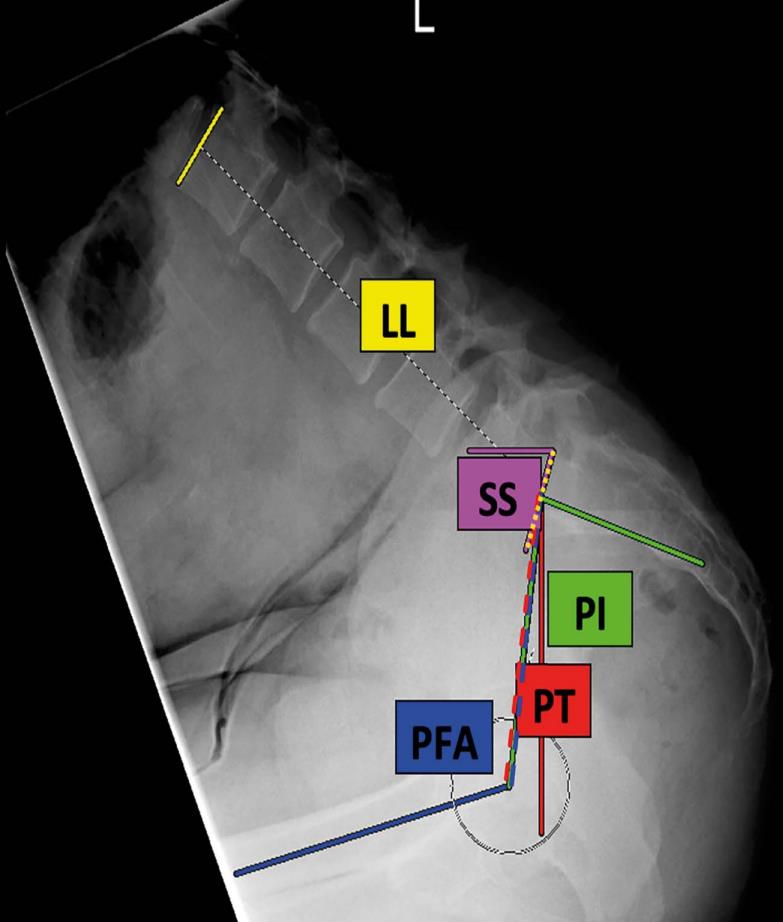

• This was a cross-sectional cohort study of 112 asymptomatic volunteers (age, 47.4 ± 17.7 years; 50.0% female; BMI, 27.3 ± 4.9 kg/m2). All participants underwent lateral spinopelvic radiography in the standing and deep-seated positions to determine maximum hip and lumbar flexion. Lumbar flexion (change in lumbar lordosis, ∆LL), hip flexion (change in pelvic-femoral angle, ∆PFA), and pelvic movement (change in pelvic tilt, ΔPT) were determined. The hip user index, which quantifies the relative contribution of the hip to overall sagittal movement, was calculated as (∆PFA/[∆PFA + ∆LL]) × 100%.